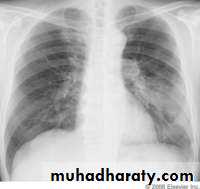

Legionnaires' disease ; No diagnostic features on the chest X-ray distinguish it from other pneumonia. But may showing pulmonary infiltrates ;Infiltrates can be unilateral, bilateral, patchy, or dense, and In sever illness it m. be multilobar involvement ,can spread very quickly to involve the entire lung.

In lobar pneumonia, a homogeneous opacity localized to the affected lobe or segment usually appears within 12-18 hours from the onset of the illness.If a complication such as parapneumonic effusion, intrapulmonary abscess formation, or empyema is suspected.